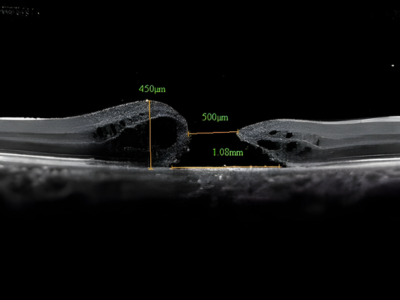

Advanced Diagnostics Testing

Using the latest diagnostic technology, including OCT (Optical Coherence Tomography) and retinal imaging, we can accurately assess your retinal health.